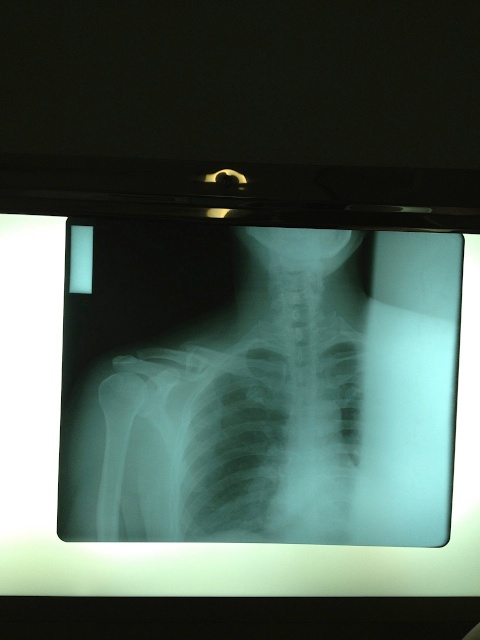

The hospital itself was an oasis of quiet and calm. I was seen immediately by a doctor who spoke perfect English, and got my x-rays taken within minutes of arriving (granted, the x-ray technician was later seen sweeping the floors, but still, he did a fine job— at both!).

It was discovered that I had broken my right clavicle in two places, one small fracture and a more serious break that compressed and made the pieces overlap like a good Boy Scout campfire setup.

| No, it’s not supposed to look like that. |